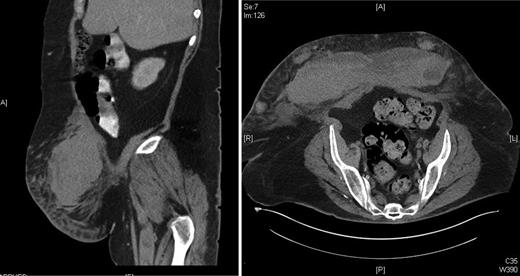

Two weeks later, the patient remained hospitalized for the management of an infected diabetic foot ulcer and awoke one morning with acute abdominal pain and shortness of breath. The patient was haemodynamically compromised with a pulse rate of 120 and blood pressure 90/60 lying. The haemoglobin fell overnight from 126 to 90 g/l and a few hours later there was a further fall to 79 g/l. The medical emergency team were called. Platelet count was 242, international normalized ratio (INR) 1.0, activated partial thromboplastin time (APTT) 33 and anti-factor Xa level 0.41 in keeping with prophylactic clexane administration. A CT scan was performed, which demonstrated a large abdominal wall haematoma (see Fig. 1).

CT abdomen of a 59-year-old obese female with an abdominal wall haematoma.